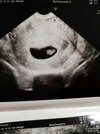

A tu zdjęcia z dziś 😍

Załączniki

• f9fcd8e6-207b-4947-8158-07f21c64aa19.jpg

f9fcd8e6-207b-4947-8158-07f21c64aa19.jpg

43,5 KB · Wyświetleń: 102

Cuuudne😍 6t6d? Jak patrzę na czyjeś zdj to takie duże mi się te wasze fasole wydają :O Albo takie fajne sprzęty wasi gin mają. Ja się przekonam w środę co zobaczę...

tak, 6t6d. Ma wielkość 1,06cm 😉 mój ginekolog faktycznie ma dobry sprzęt 🙂 pewnie i u Ciebie będzie widac już co nie co😉który to będzie tydzień?